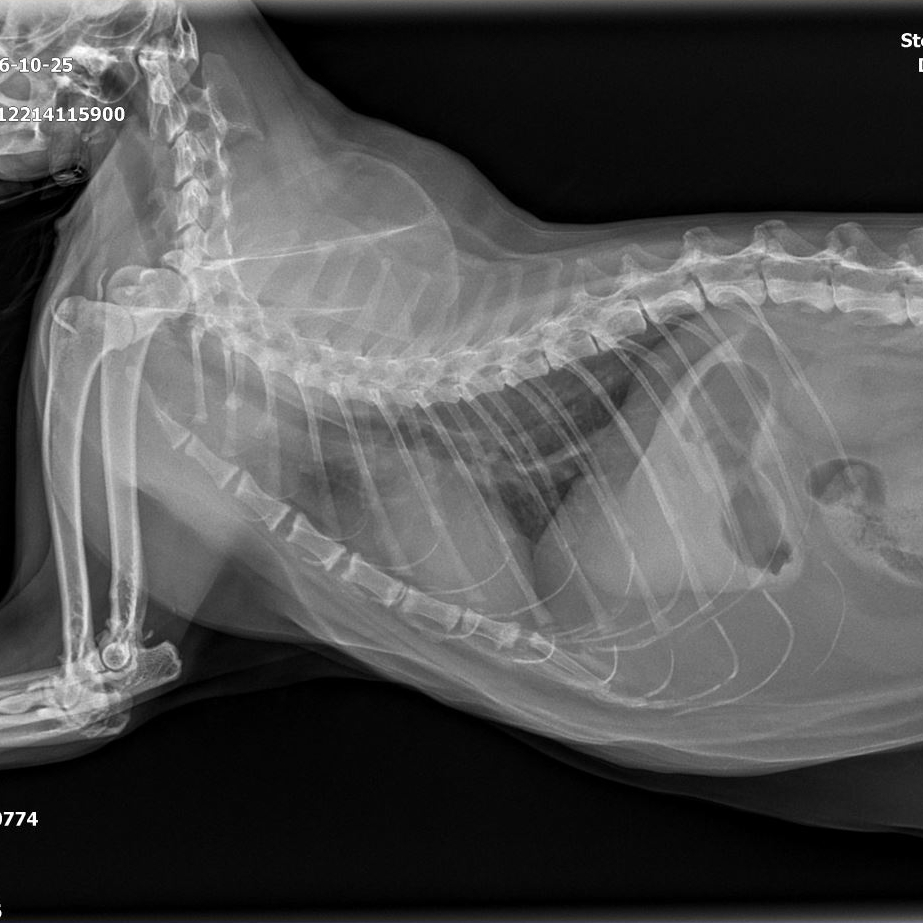

<내원 당시 환자 상태>·코리안숏헤어, 14세·갑상선기능항진증 #갑상선기능항진증 #고혈압·심근비대증(HCM)·4년차 갑상선기능항진증 #갑상선기능항진증(HCM)·4년차 갑상선기능항진증 관리 중,

내원한 환자는 주치의병원에서 4년 전 갑상선기능항진증과 심근비대증(HCM)을 진단받았고 이후 꾸준히 갑상선약, 심장약을 투약해 왔습니다.최근 환자가 다시 불안해하면서 갑상선 호르몬 수치가 다시 증가하는 것으로 확인됐습니다.갑상선약을 조정하였으나 호르몬 수치가 정상적으로 회복되지 않아 주치의와 상담 후 방사성 요오드 치료를 위해 헬릭스 동물 메디컬센터에 내원하게 되었습니다.갑상선 기능 항진증은 주로 어떤 질병인 것입니까?고양이들, 노령고양이에게 흔히 발생하는 갑상선기능항진증(갑기항)은 갑상선호르몬 과다분비가 일어나는 질병입니다.

환자는 헬릭스동물메디컬센터에 초진 내원하여 종합검사를 실시하여 현재 환자의 몸 상태와 호르몬 수치를 정확히 파악하였습니다.

- 내원 및 전신상태평가 예약을 통해 내원하면 신체검사, 혈압측정, 호르몬검사, 전해질, 소변검사, 영상검사를 실시하여 환자의 전신상태를 평가합니다.